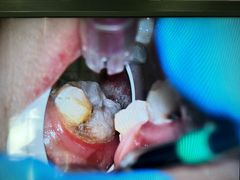

• 希望齿科(河西店)

• -希望齿科(河西店)